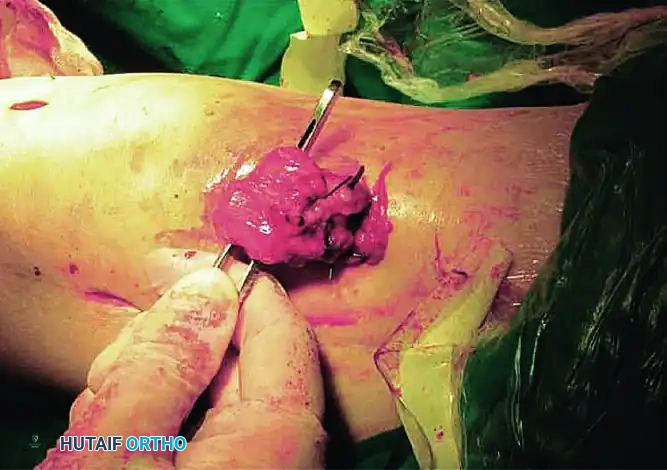

STAGE 5: Quadriceps Tendon Lengthening

For severe arthrofibrosis, the fifth stage is mandatory to gain more than 90 degrees of flexion.

- Transect the rectus femoris at a more distal level than the vastus intermedius, adjacent to its patellar insertion.

- Deliver the free tendinous ends of the vastus intermedius and the rectus femoris through the surgical wound.

- Gently manipulate the knee in flexion repeatedly until maximal passive flexion is achieved.

- Overlap the proximal tendinous end of the vastus intermedius and the distal portion of the rectus femoris tendon.

- Suture the overlapped tendons using a No. 2 nonabsorbable braided suture (e.g., Ethibond) with the knee held strictly in 90 degrees of flexion.

Dynamic Tensioning Pearl: Test the passive range of motion after repairing the quadriceps tendon. The lengthened tendon must be under substantial tension but remain competent at 90 degrees of flexion.

- If the knee flexes easily beyond 90 degrees: Increase the overlapping of the tendons by advancing the vastus intermedius tendon more proximally. This reduces the risk of a severe postoperative extension lag.

- If flexion is restricted: Decrease the overlapping by fixing the vastus intermedius tendon more distally.